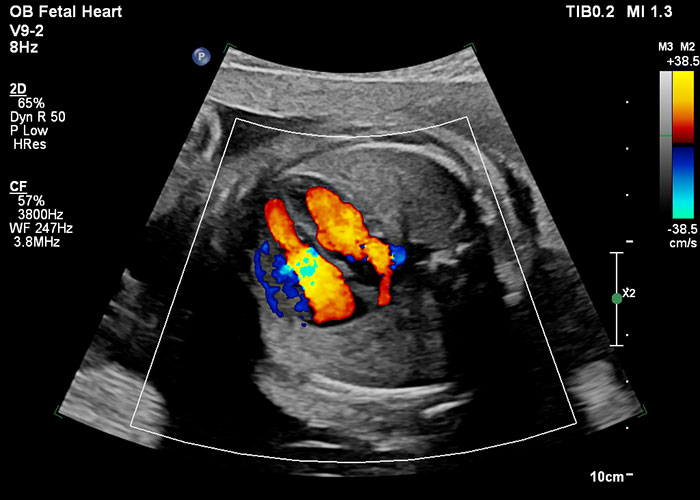

Uno de los avances más sofisticados en la imagenología pediátrica es la capacidad de detectar anomalías fetales en el útero, especialmente defectos del corazón relacionados con la enfermedad cardíaca congénita. Aproximadamente 1 de cada 100 bebés nace con cardiopatía congénita y un tercio de estos niños se someterá a una intervención quirúrgica o a una intervención basada en catéteres durante el primer año de vida. [i] Cuando estás anomalías se detectan temprano, los niños tienen una mayor probabilidad de celebrar más cumpleaños que cuando no se detectan sino hasta más tarde en la vida.

Imagen de ultrasonido que ilustra un corazón fetal a las 28 semanas Seguimos innovando en esta área e incluso hemos desarrollado soluciones que incorporan resonancia magnética para abordar anomalías congénitas en el útero. Esta innovación en imagenología cardíaca fetal está ayudando a obtener imágenes de patologías complicadas incluso antes de que nazca el bebé. Esto puede permitir que la planificación del tratamiento comience mientras el bebé está en el útero, lo que les da la mejor oportunidad de obtener el mejor resultado posible. Estas innovaciones son tan emocionantes porque si una anomalía se detecta a tiempo, hoy en día, algunas cirugías incluso se pueden hacer en el útero para corregir defectos cardíacos, lo que mejora los resultados puesto que los niños se recuperan mejor mientras aún están inmersos en líquido amniótico. [i],[ii],[iii] Detectar las anomalías cardíacas de manera temprana también ayuda a prevenir complicaciones al nacer puesto que las madres pueden planificar dar a luz en hospitales equipados para manejar cualquier complicación esperada, lo que le da a su bebé la mejor oportunidad de supervivencia.

Si en una ecografía prenatal se encuentra algo que justifica una mayor investigación, o si el feto tiene un mayor riesgo de una anomalía cardíaca, entonces se justifica la ecocardiografía cardíaca fetal para detectar dichas anomalías. El ecografía fetal, que utiliza transductores y aplicaciones diseñadas específicamente para detectar anomalías en el corazón fetal, se utiliza para el diagnóstico de las anomalías congénitas más complicadas. Durante el eco fetal, los médicos pueden evaluar la estructura y la función del corazón del bebé, al examinar un objeto del tamaño de una almendra que late unas 150 veces por minuto, en busca de pequeños agujeros y conexiones. A medida que la tecnología ha madurado, vemos que las innovaciones en la ecografía fetal crean exploraciones de mayor precisión, al tiempo que optimizan el flujo de trabajo para que los transductores sean más fáciles de usar para los médicos.